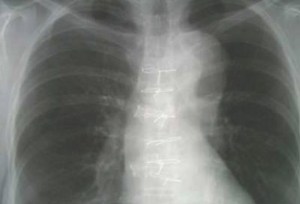

His WBC was 6,700 cells per mcL (65% neutrophils). The blood cultures flagged positive for a Gram-negative rod and the admission chest X-ray is shown below.

A rather difficult case to guess, perhaps. But this patient had a normal WBC with normal differential counts despite having Gram-negative bacteraemia, and one of the few types of Gram-negative rods where such a phenomenon is observed is Salmonella spp. Given the elderly patient and the aortic dissection seen on the chest X-ray, this is likely non-typhoidal Salmonella bacteraemia with infected aortic aneurysm/dissection. A CT image is shown below.